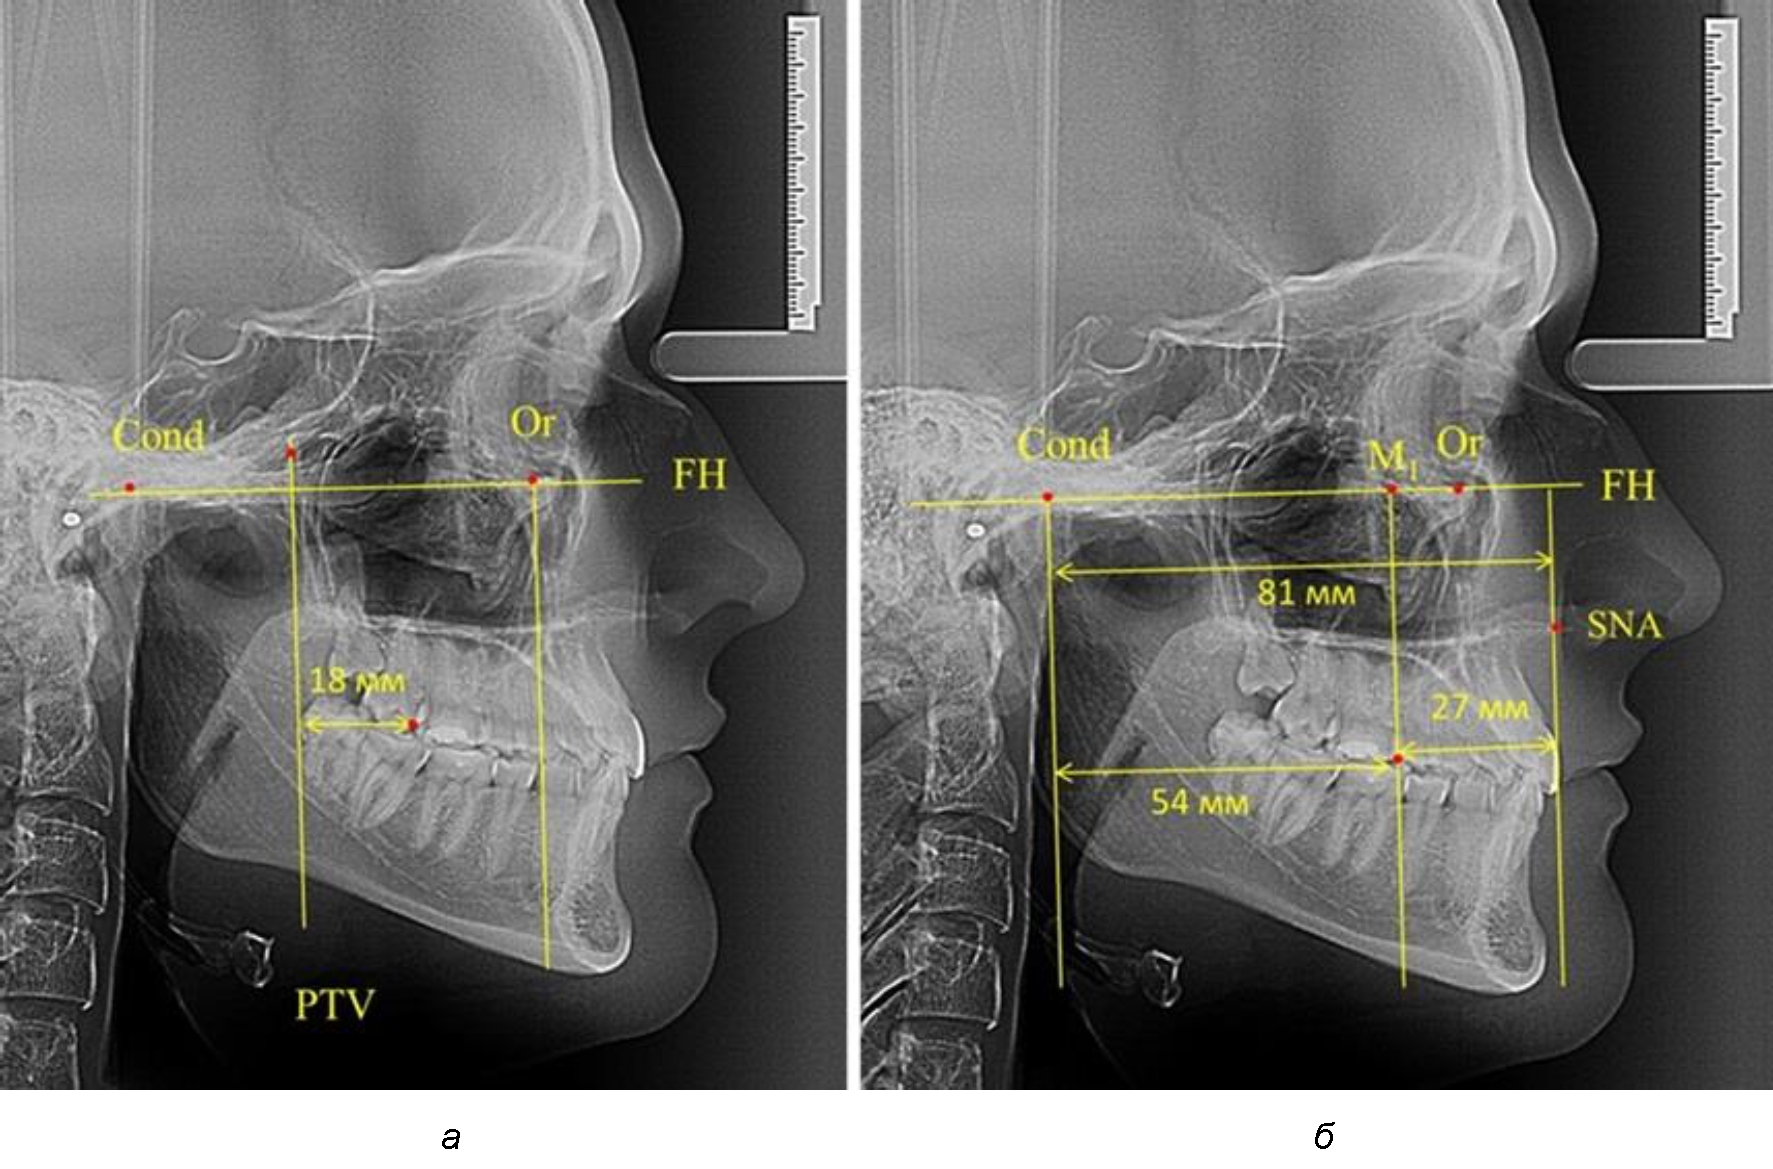

По мере роста челюстей увеличивалась глубина гнатического отдела лица, и кондиллярно-спинальный размер составлял в среднем (74,57 ± 0,93) мм. Дистальная поверхность первого постоянного моляра отстояла от крыловидной вертикали на величину, составляющую около 11 мм, что, так же, как и в периоде прикуса молочных зубов, было близким по значению к данным R. E. McDonald, а именно возраст, плюс 3 мм. Однако величина ошибки среднего значения свидетельствовала о вариабельности признака даже в восьмилетнем возрасте после замены передней группы зубов и установки ключевых постоянных моляров в окклюзионное равновесие. Обращает на себя внимание отношение глубины гнатического отдела лица к дистальному отделу, а именно к кондилярно-молярному расстоянию (рис. 5).

Рис. 5. Особенности положения первых моляров по R. E. McDonald (а) и по предложенному методу (б) у ребенка 8 лет

После прорезывания вторых постоянных моляров кондилярно-спинальный увеличивался до 80 мм.

Дистальная поверхность первого постоянного моляра отстояла от крыловидной вертикали на величину, составляющую около 18 мм, что, так же, как и в предыдущих периодах прикуса, было близким по значению к данным R. E. McDonald, а именно возраст, плюс 3 мм.

Обращает на себя внимание отношение глубины гнатического отдела лица к дистальному отделу, а именно к кондилярно-молярному расстоянию, которое, вне зависимости от сагиттальных размеров, составляло 1 : 1,5.